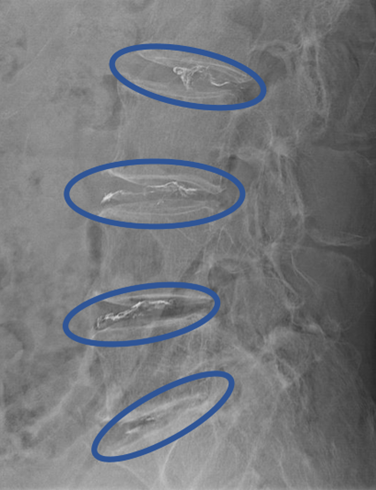

患者様と相談の元、2/3,3/4,4/5,5/s にセルゲル法を施行

DiscoGelを入れた後の画像になります。

治療は 40分 程度で終了

回復室で休憩後、歩いて帰院されました。